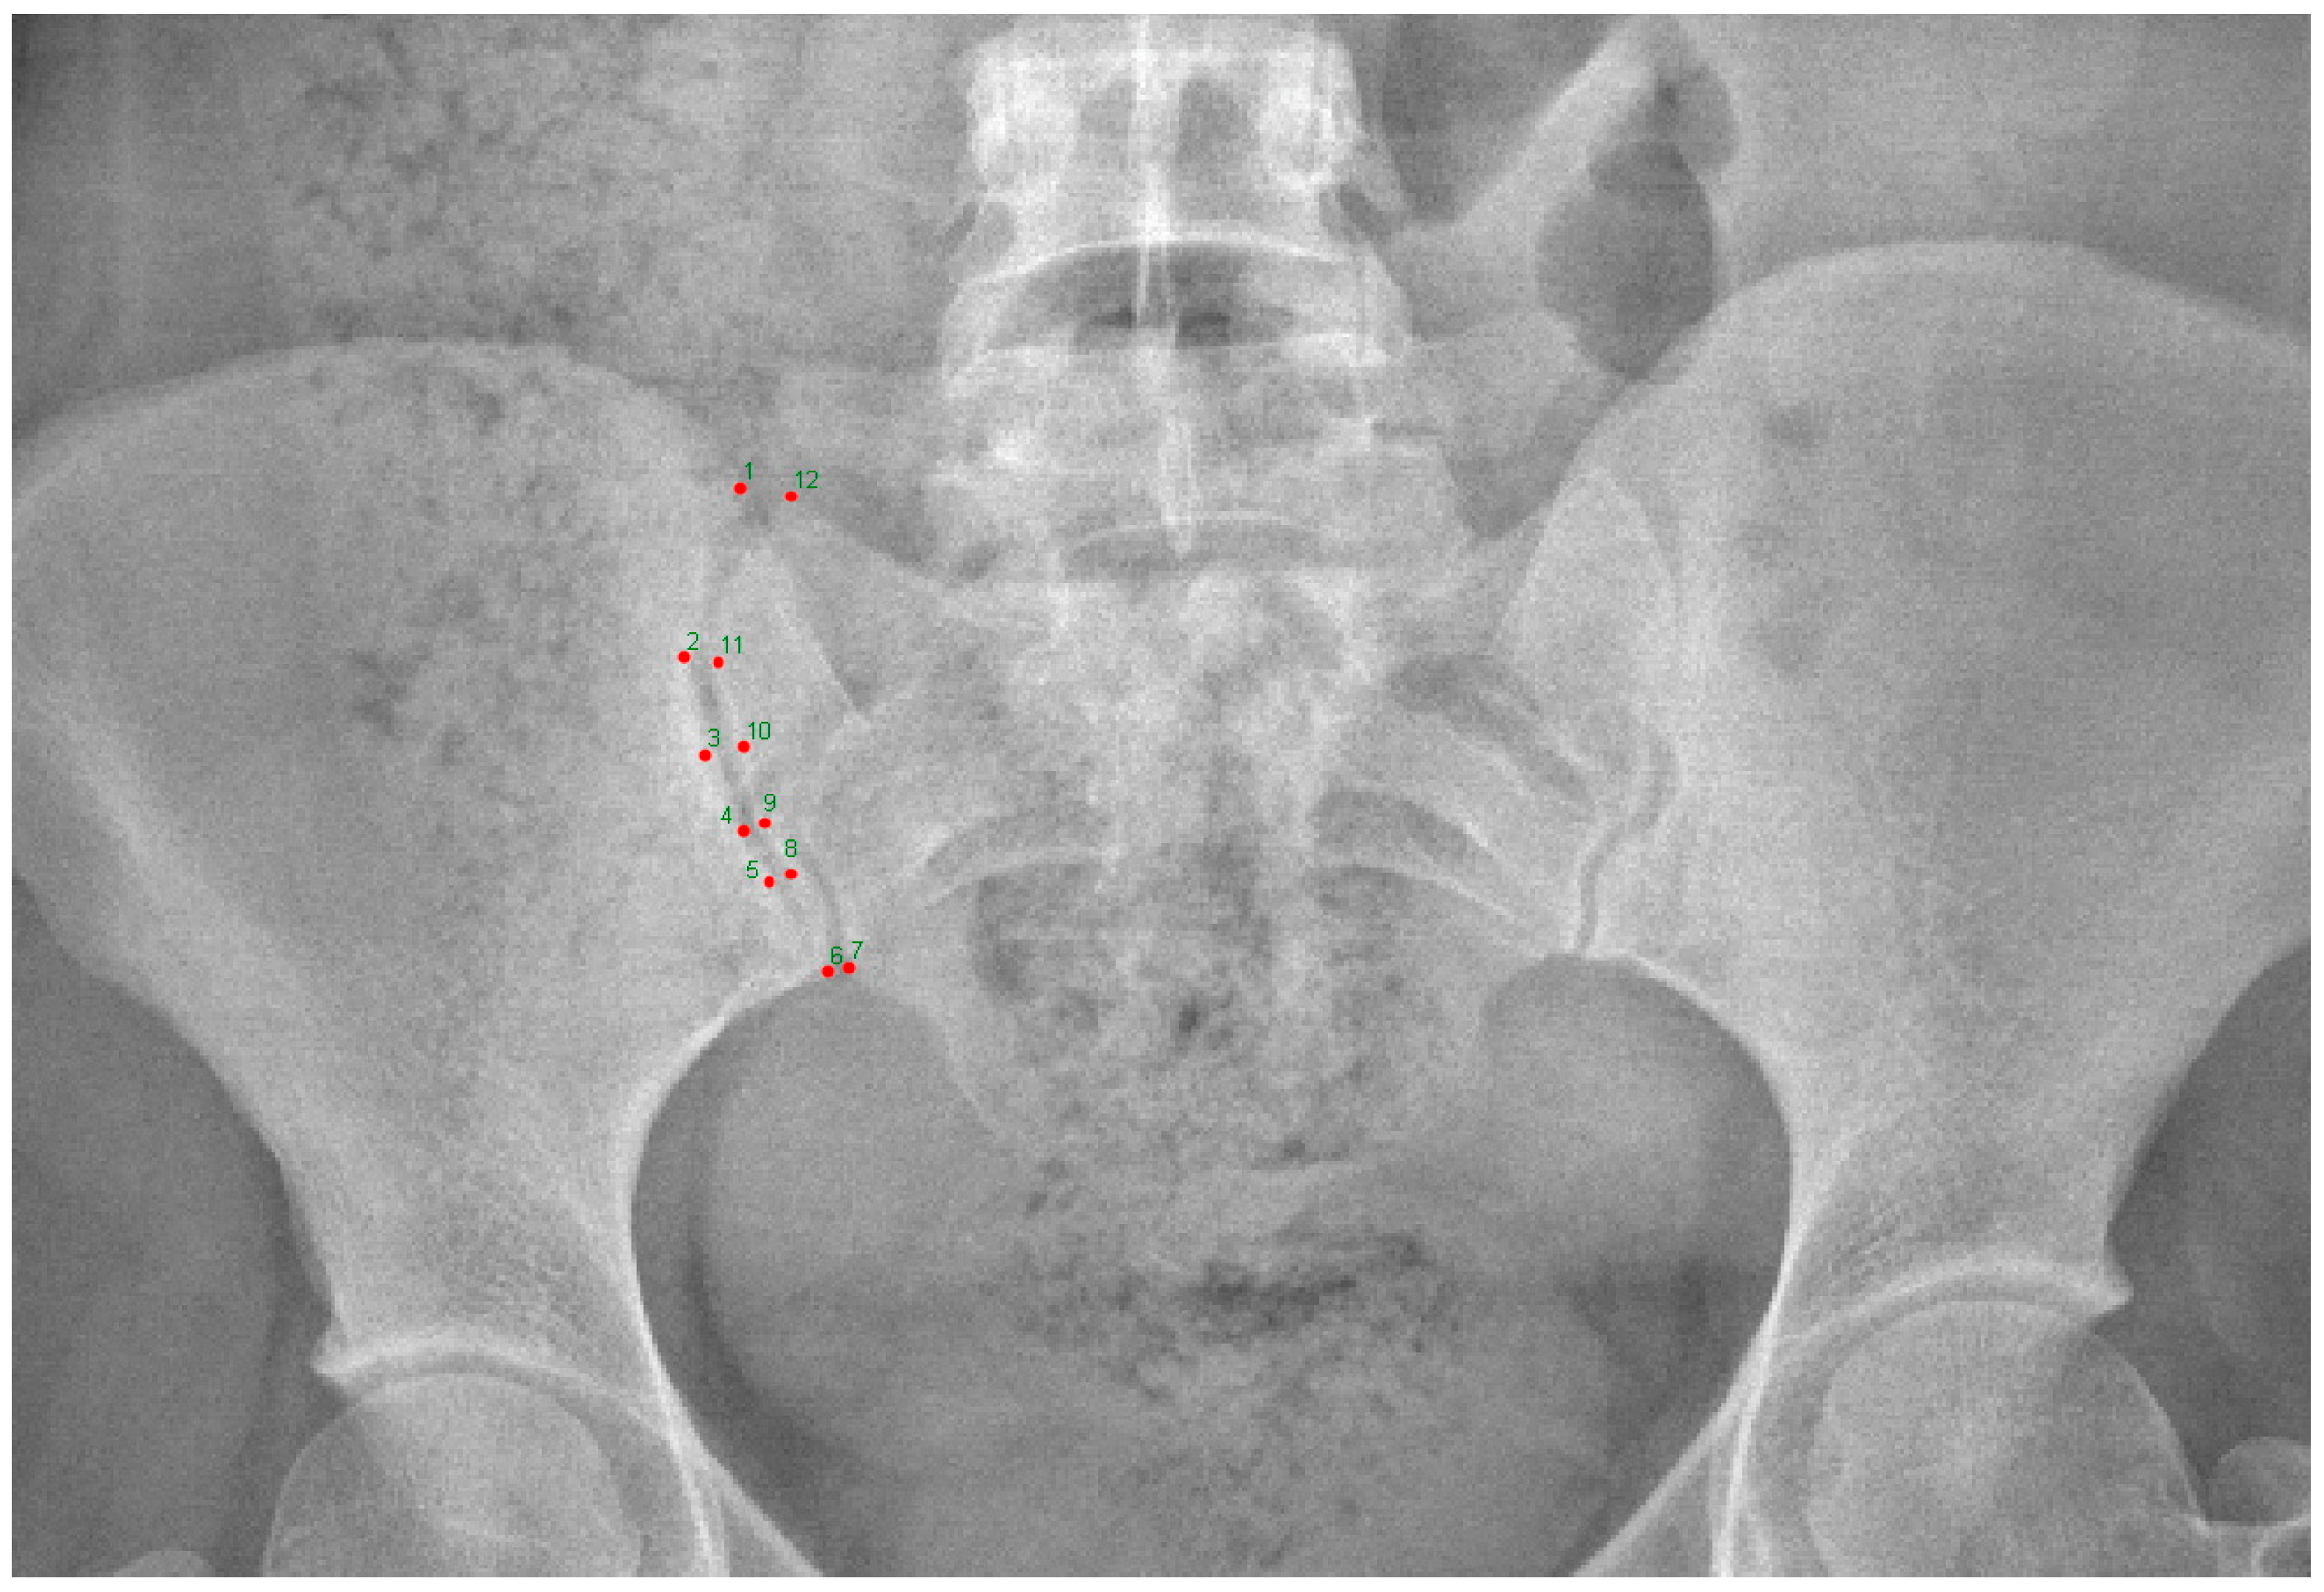

| Landmark Number | Description |

|---|---|

| Landmark 1 | Superior tip of iliac crest at the SIJ |

| Landmark 2 | The most anterior part of SIJ on the iliac side |

| Landmark 3 | Middle point of SIJ on the iliac side |

| Landmark 4 | Upper 1/3 of the inferior half of SIJ on the iliac side |

| Landmark 5 | Lower 1/3 of the inferior half of SIJ on the iliac side |

| Landmark 6 | The most inferior point of the SIJ on the iliac side |

| Landmark 7 | The most inferior point of the SIJ on the sacral side |

| Landmark 8 | Lower 1/3 of the inferior half of the SIJ on the sacral side |

| Landmark 9 | Upper 1/3 of the inferior half of the SIJ on the sacral side |

| Landmark 10 | Middle point of the SIJ on the sacral side |

| Landmark 11 | The most anterior part of the SIJ on the sacral side |

| Landmark 12 | Superior tip of the SIJ on the sacral side |